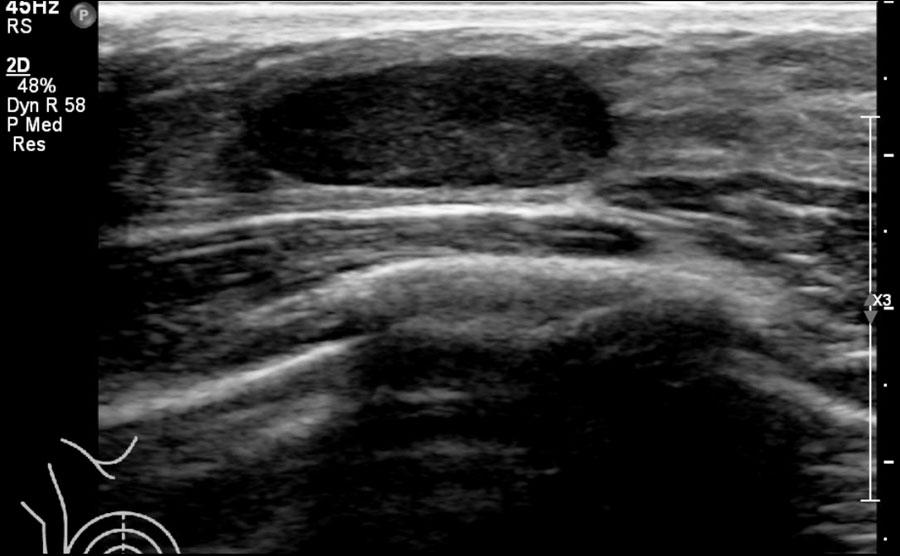

Đây là hình ảnh siêu âm bình thường của tuyến vú.

Lớp xám phía trên là da.

Tiếp theo là sự pha trộn giữa mô mỡ (tối hoặc giảm âm) và mô tuyến (xám sáng hoặc tăng âm).

Lớp có vân sọc phía sau mô vú là cơ ngực.

Phía sau hoặc sâu hơn so với xương sườn có một vùng đen hay bóng cản âm phía sau.

Phổi là lớp có thể quan sát sâu nhất.

Không khí trong phổi phản xạ hầu hết sóng âm, tạo ra một đường sáng hoặc tăng âm với bóng cản bẩn phía sau.